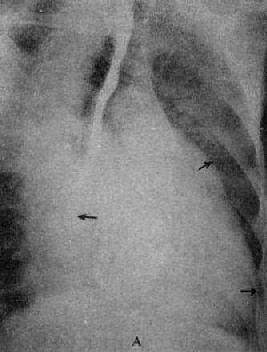

单纯二尖瓣狭窄X线表现(图3-2-15)为:①心脏增大,左心房和右心房增大,左心耳常明显增大;②主动脉球缩小,主要原因是左心室血液排出量减少,主动脉发育障碍或心和大血管向左旋转时,主动脉弓折叠;③左心室缩小,心尖位置上移,心左缘下段较平直;④二尖瓣瓣膜钙化,系直接征象;⑤肺瘀血和间质性水肿。上肺静脉扩张,下肺静脉变细。有时还可见肺野内出现直径1~2mm大小的颗粒状影,为含铁血黄素沉着。

图3-2-15 二尖瓣狭窄

A.右前斜位:右心室增大,肺动脉段突出(↑),心前间隙变窄(↑),左心房轻度增大;B.后前位:心增大,呈二尖瓣型,右心室增大,肺动脉段突出,左心耳增大,出现第三弓(↓),有肺瘀血表现;C.左前斜位:右心室增大,左心房增大不明显;左心室不增大。